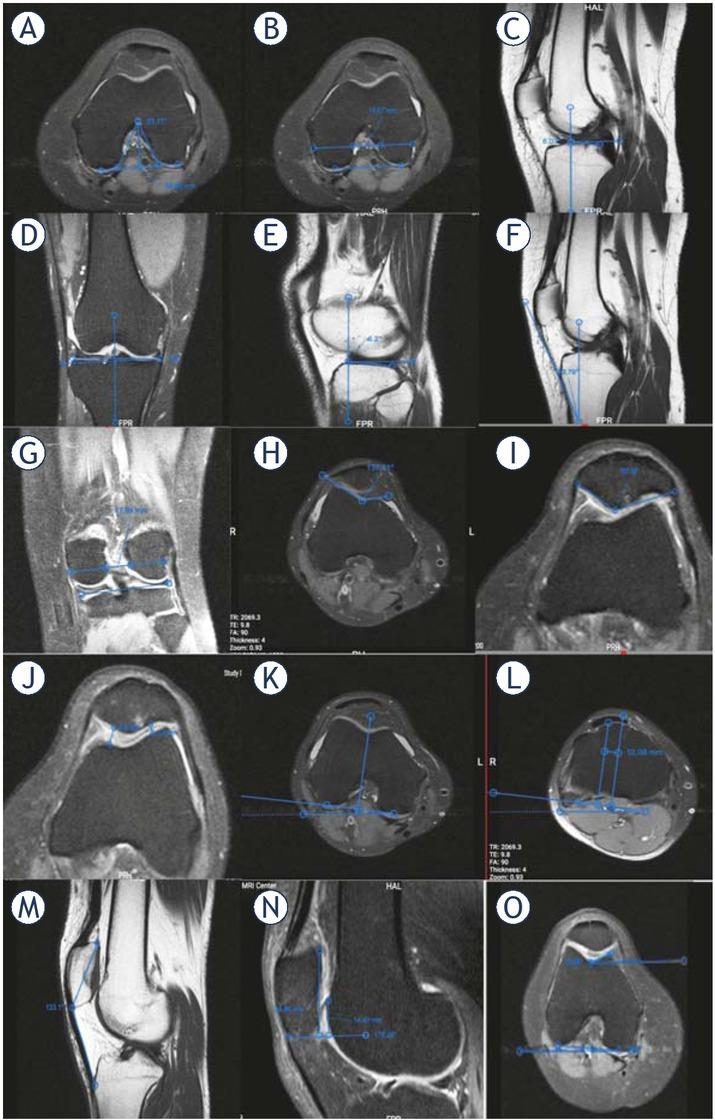

Figure 2